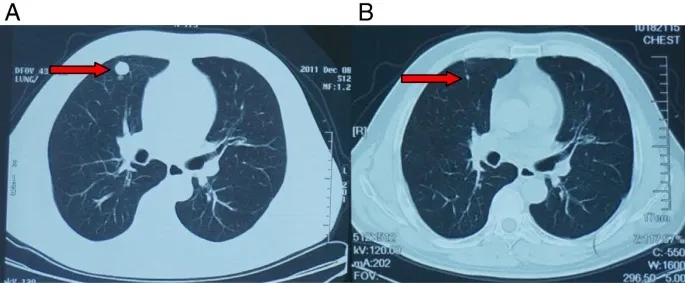

值得关注的是,其中一例肾癌肺转移患者,经治疗后肿瘤体积显著缩小(详见下图:图A为治疗前肺转移灶,图B为治疗后肺转移灶)。

▲图源“BCM”,版权归原作者所有,如无意中侵犯了知识产权,请联系我们删除